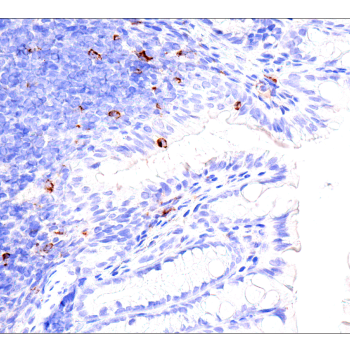

使用 PD-L2 (D7U8C™) XP® Rabbit mAb 对石蜡包埋的人纵隔大 B 细胞淋巴瘤进行免疫组织化学分析。